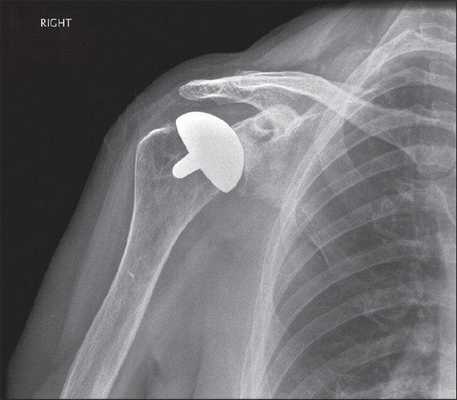

Обратный или реверсивный используется, когда вращательная манжета не функционирует и нарушена стабильность. Тогда головка крепится к суставной впадине (гленоидальному компоненту), а вогнутый имплантат впадины на ножке фиксируется на плечевой кости.

Для однополюсного эндопротезирования используются гемипротезы, то есть заменяющие только одну часть сустава. По способу установки делятся на поверхностные и штыревые (внедряются в кость).